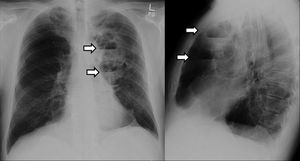

Posterior-anterior and lateral view chest x-ray shows an oval anterior and medial opacity, with 2 well defined air-fluid levels in the left lung which is seen at the arrows i have seen this case in a journal but i cant remember the name.. in this case Air-fluid levels within emphysematous lung bullae are a relatively uncommon occurrence in patients with preexisting bullous disease and it is not commonly reported... .